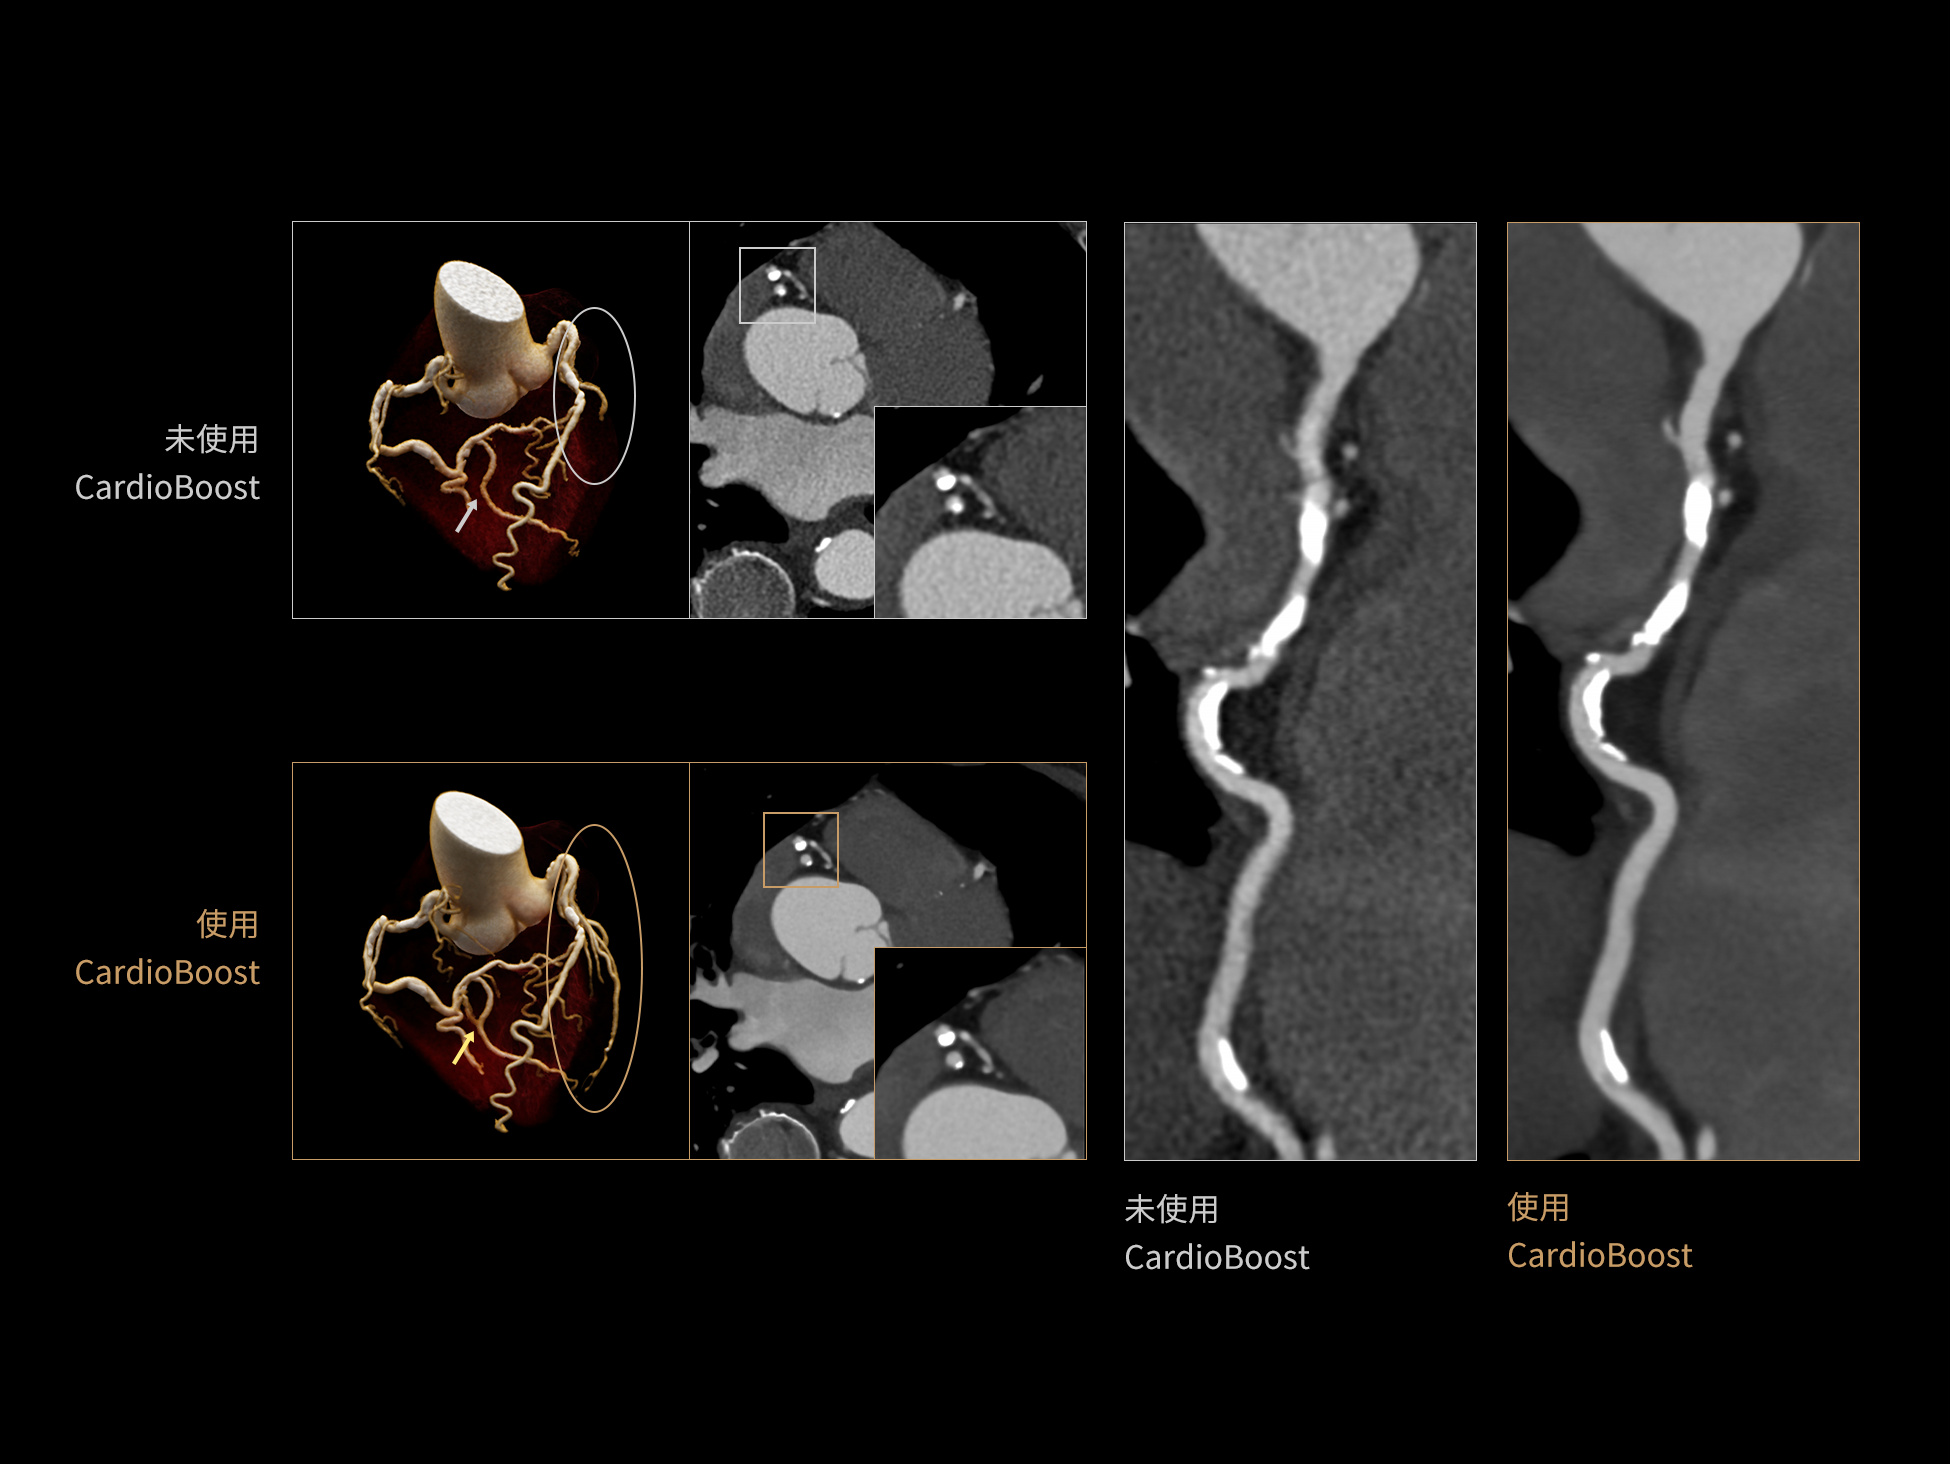

uCT 868 搭载联影最新一代 uSense 人工智能平台,将智能化深度融入 CT 扫描全流程,从感知细微生理运动到精细结构探测,再到多场景诊疗优化。以 AI 为核心驱动力,uSense 重塑成像各环节,打造高效、高清的智慧扫查体验。在心脏成像领域,uSense 结合宽体探测器、心脏专研AI重建算法与AI冠脉运动追焦技术,在保持低剂量的同时,有效抑制运动伪影,精准呈现软斑块、混合型斑块及支架细节,助力冠脉成像惠及更多患者。针对多科室疾病临床应用场景,uSense 平台提供全方位的智能解决方案:包括头部运动伪影智能校正、金属植入物伪影抑制、扫描视野扩展等先进算法。这些创新技术使 uCT 868 能够构建覆盖全场景的智能诊疗体系,持续拓展 AI 赋能医学影像的边界。